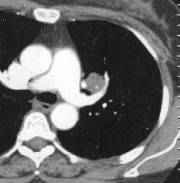

肝癌肺转移(3)肺部其他恶性肿瘤如肺原发肉瘤、肺癌肉瘤等。常症状轻微甚至无症状就诊时间 较晚,X线及CT表现为圆形、椭圆形肿块,边缘光滑,分叶多不明显,可为小切迹样或铸 型表现,直径多达6〜7cm,大者可占据一叶肺甚至一侧胸腔(图4)。增强肿块呈不规则

明显强化,表面常有包膜或假包膜。极少有肺门纵隔淋巴结转移。 医学百科网 | YxBaike.Com